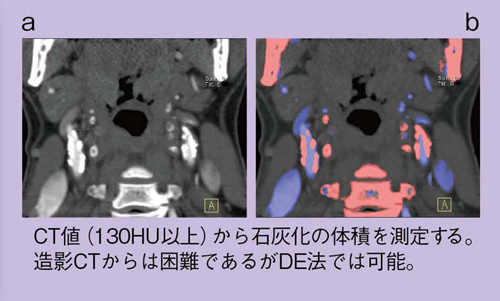

スペクトラルCT 基本原理と臨床応用』 | 学研出版サイト

スペクトラルCT 基本原理と臨床応用』 | 学研出版サイト,

スペクトラルCT 基本原理と臨床応用』 | 学研出版サイト, Dual Energy Imaging ~頭頸部領域での臨床応用~ - シーメンス・ジャパン株式会社 - inNavi Suite,

Dual Energy Imaging ~頭頸部領域での臨床応用~ - シーメンス・ジャパン株式会社 - inNavi Suite, IQon スペクトラル CT - 64列/128スライス/2層構造 - 株式会社フィリップス・ジャパン,

IQon スペクトラル CT - 64列/128スライス/2層構造 - 株式会社フィリップス・ジャパン, シーメンスヘルスケア株式会社】 CT装置 Dual Energy Imagingの原理と解析の基礎 -放射線技師向け情報サイト│ラジくる,

シーメンスヘルスケア株式会社】 CT装置 Dual Energy Imagingの原理と解析の基礎 -放射線技師向け情報サイト│ラジくる, SPECTRAL CT 新たな局面を迎えたラボ用X線マイクロCT | 東陽テクニカ | “はかる”技術で未来を創る | ナノイメージング,

SPECTRAL CT 新たな局面を迎えたラボ用X線マイクロCT | 東陽テクニカ | “はかる”技術で未来を創る | ナノイメージング,